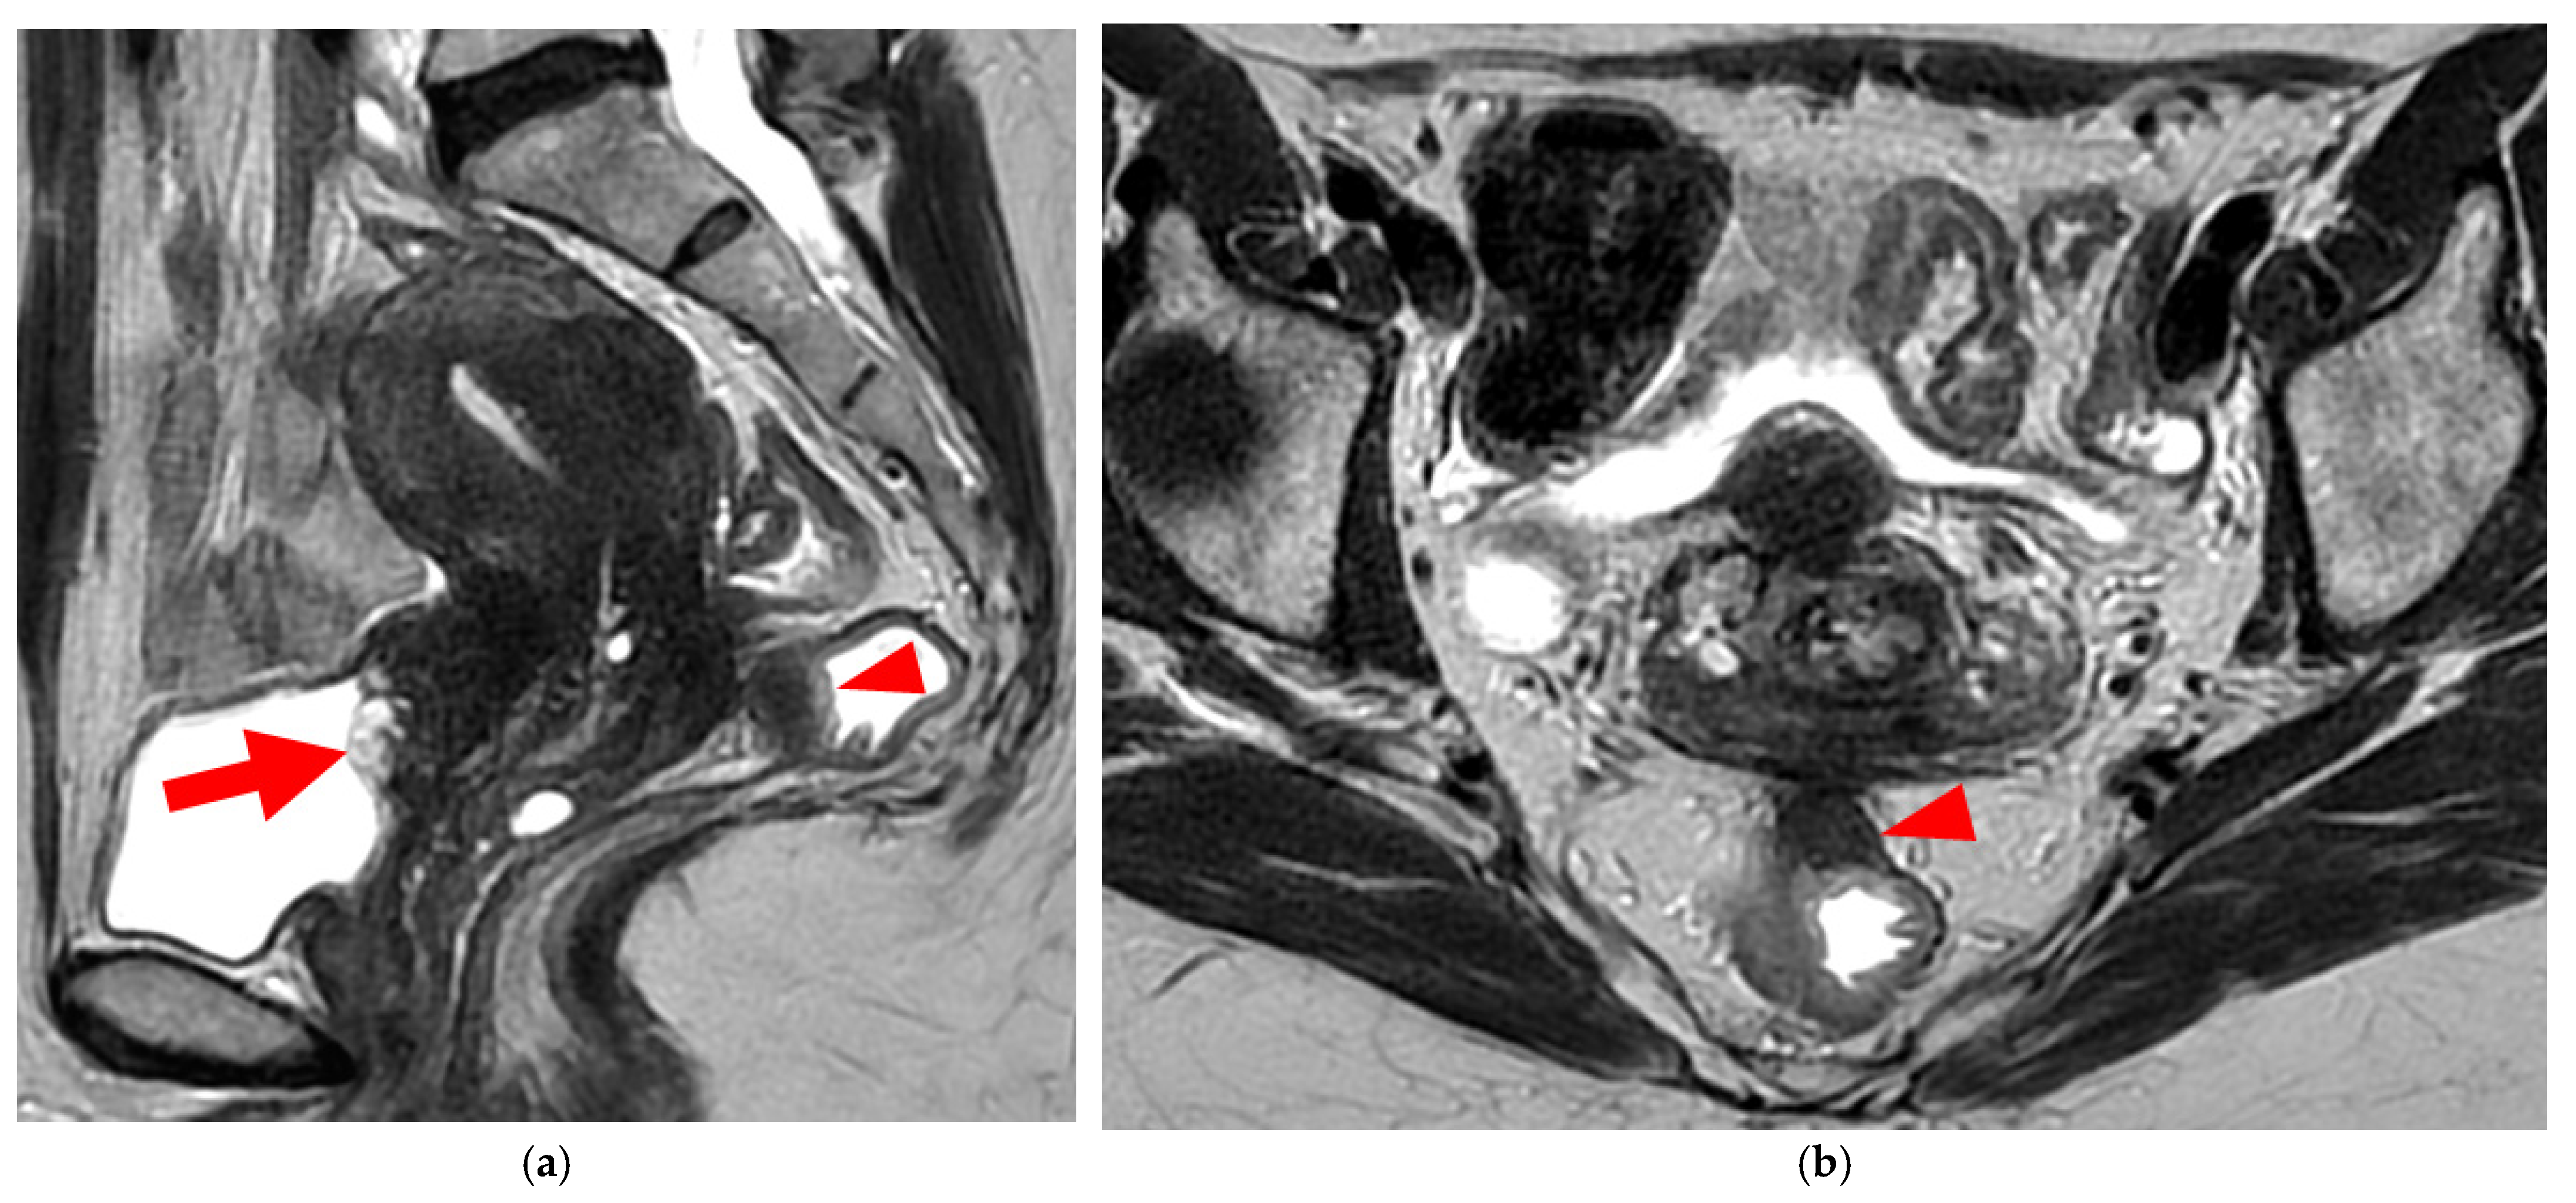

A type 6 USL is associated with adjacent pelvic “visceral” involvement in a broad sense. It most commonly affects the digestive tract (Figure 8 and Figure 9), with the rectum and rectosigmoid junction wall thickening: in this case, the lesion often appears as a “medallion-shaped” protrusion into the lumen. Less frequently, the urinary tract is affected (Figure 9 and Figure 10), involving the muscular layer of the bladder or even the distal ureter at the level of the common iliac artery, with stenosis potentially leading to upstream hydronephrosis. More rarely, as USLs are also close to nearby pelvic nerve structures (Figure 11), contiguous involvement of the inferior hypogastric plexus located in the sacro-recto-genital septum (a.k.a. Delbet sagittal fascia) beneath the distal two-thirds of the USL, or exceptional involvement of the sciatic nerve adjacent to the pelvic wall, is possible (Figure 12, Figure 13 and Figure 14).

2.3.1. “Kissing Ovaries”: A Form Straddling Between Type 5B and Type 6 USLs

Besides endometriomas, another type of ovarian involvement in DIE includes adhesions that cause the ovaries to retract medially across the midline, behind the uterus, into the pouch of Douglas. When the ovaries are displaced medially and are in close proximity, they are commonly referred to as “kissing ovaries”. Additionally, medialized ovaries on preoperative imaging expose the digestive tract to a 20% risk of involvement [22]. In our experience, the injection of a contrast agent is useful when there is doubt about an endometriotic rectosigmoid invasive lesion on T2WI, especially if a rectal filling was not performed. A markedly enhancing mucosa, which outlines rectosigmoid local wall thickening on post-contrast T1WI without fat suppression (forming a “medallion-shaped” lesion), is a valuable aid to diagnosis.

In the HTD MRI classification of USLs, the “kissing ovaries” sign is considered a form between types 5B and 6. In the case of concomitant rectal involvement, the USL is classified as type 6 (Figure 15); otherwise, it is classified as type 5B (comparable to a nodule with spiculated margins).

Figure 15. Pelvic MRI scan of a patient with a “kissing ovaries” sign and rectal involvement (i.e., HTD type 6 USLs). (a,b) Axial T2WI (a) and contrast-enhanced T1WI (b) show both ovaries in close proximity (“kissing ovaries” sign) (arrowheads) and rectosigmoid wall infiltration (arrows). (c) Sagittal contrast-enhanced T1WI shows rectosigmoid wall infiltration, appearing as a “medallion-shaped” lesion outlined by markedly enhancing mucosa (arrowhead).